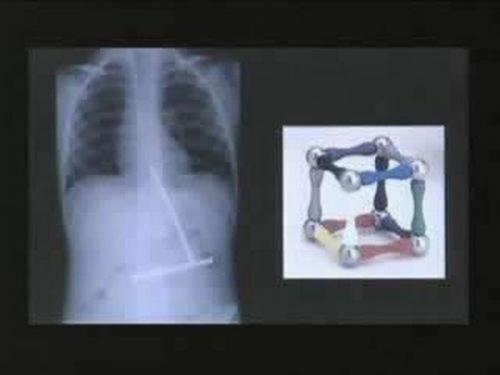

Магнитная головоломка